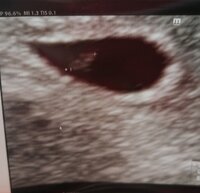

Ultrassa käyty, vastasi 5+5, kuten joku täällä laski. Nappiin laskettu :dummy1::dummy: sykettä ei näkynyt vielä, 2vk ja uusi ultra, se onkin ilmainen :)

Täällä varhaisultra takana ja hän löytyi oikeasta paikasta, oikean kokoisena :love7 Sykekin näkyi hienosti :Heartred Tänään viikkoja 6+4.